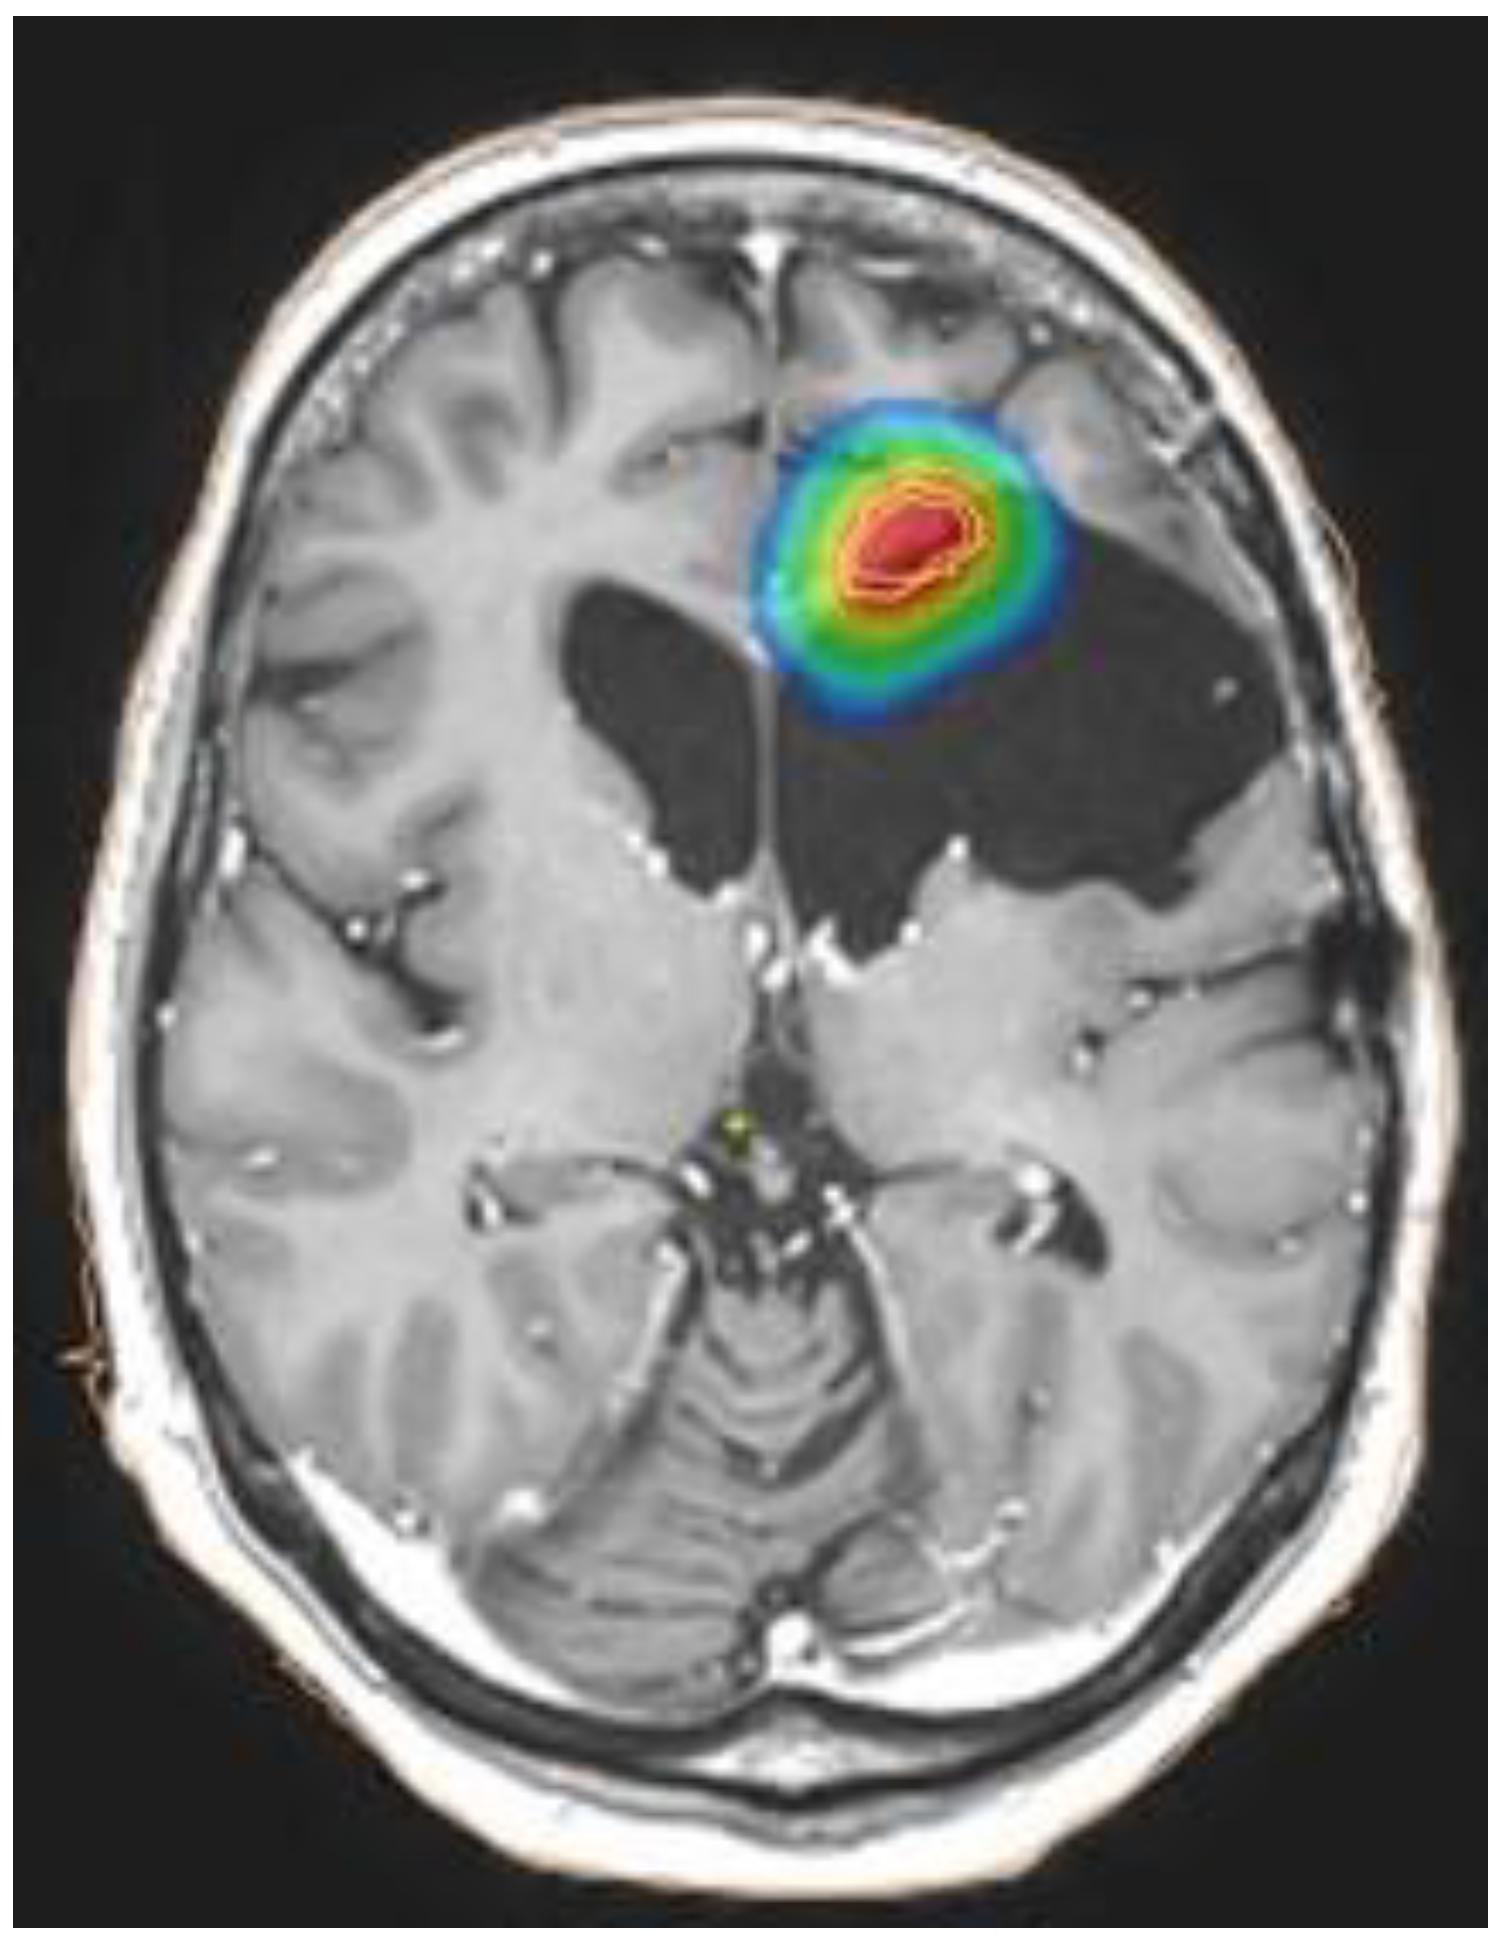

A review published in 2018 showed that the volume of the target influences the risk of toxicity and, consequently, the choice of fractionation: radiosurgery with EQD2 < 65 Gy may be a choice for small lesions (target volume < 12.5 mL, Figure 2), hypofractionated stereotactic radiotherapy with EQD2 < 50 Gy is feasible for medium lesions (target volume up to 35 mL), whereas conventionally fractionated treatment with EQD2 < 36 Gy may be used for reirradiation of large lesions (target volume up to 50 mL).

Figure 2.

Example of dose distribution for small lesion treated with stereotactic radiotherapy: the colors correspond to an EQD2a/b = 2 of blue > 8 Gy; green > 30 Gy; yellow > 40 Gy; red > 50 Gy.